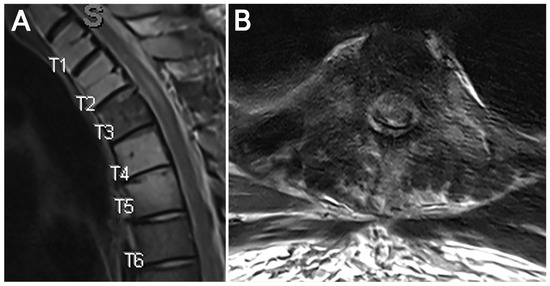

Using Endoscopic Approaches in the Surgical Management of Spinal Metastatic Disease

Patients with spinal metastasis often benefit from surgical intervention for debulking to improve neurologic deficits, reduce spinal cord or root compression, and ameliorate pain. Traditionally, large, open fusions have been used to achieve adequate decompression of neural structures. These types of interventions are frequently associated with significant blood loss, prolonged hospitalizations, and increased risk of surgery-related complications, which can delay postoperative chemotherapy and radiation therapies. Endoscopic spine approaches allow access to the spinal cord and nerve roots with minimal soft tissue disruption, which has been shown to reduce risks associated with open surgery in other contexts. Furthermore, the smaller incision, reduced blood loss, ability to position incisions away from radiation fields, and lower risk profile in high-risk patients may provide an effective solution to spinal metastases in appropriately selected cases. Here, we present two cases of spinal metastases successfully managed with spinal endoscopy and recommend the consideration of this approach for similar scenarios. Full article